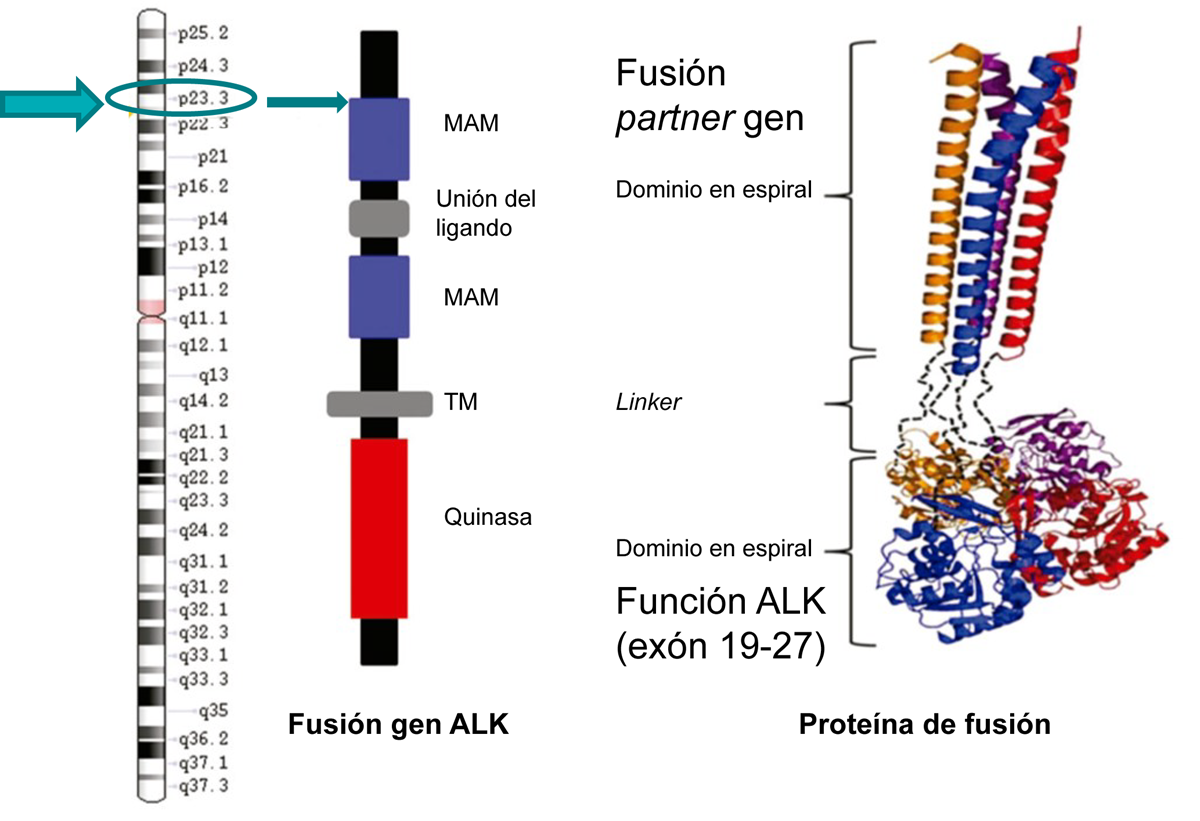

El gen ALK está localizado en el brazo corto del cromosoma 2 (2p23), pertenece a la superfamilia de receptores de insulina y codifica para la proteína ALK.1

ALK es un receptor tirosin quinasa formado por:1

- Una región extracelular con dominios meprina-A5-μ (MAM).

- Un fragmento TM.

- Una porción citoplasmática (dominio TK).

Figura adaptada de la figura 1 de Du X, et al. Thorac Cancer. 2018.1

En el cáncer de pulmón ALK+ se produce un reordenamiento del gen ALK con diferentes partners, generando una proteína de fusión anómala que activa el dominio tirosin quinasa de ALK y a un aumento en el crecimiento de las células cancerosas3. Este reordenamiento de ALK está presente en el ~4% del CPNM4.